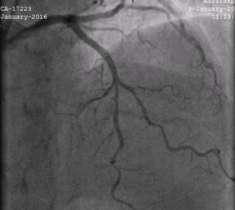

Sirolimus Eluting BioResorbable Vascular Scaffold System